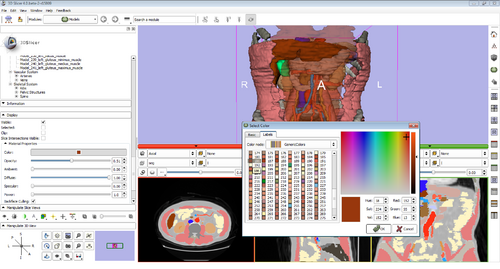

Slicer

Modules